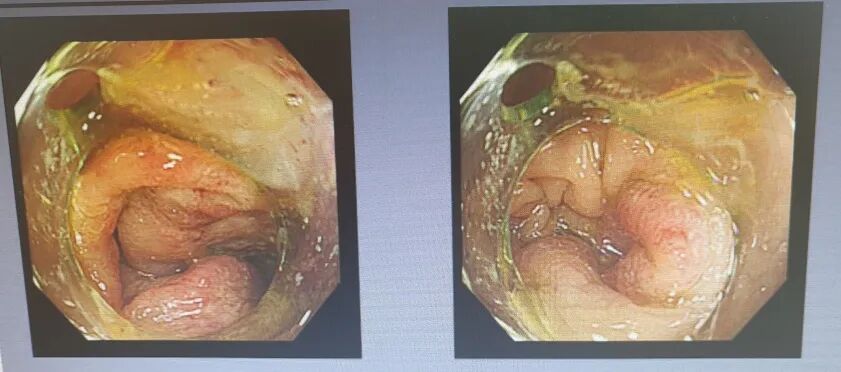

一个多月来,间断性的腹痛一直困扰着何先生。在我院行肠镜检查,结果不容乐观:进镜至26cm处,发现肿瘤已然环绕肠腔生长,导致肠镜无法通过。随后行增强CT检查,不幸中的万幸是肿瘤尚未发生远处转移,但已引发不完全性肠梗阻和肠狭窄。结合病理活检确诊为腺癌,临床诊断明确,需尽快实施手术切除病灶,避免病情进一步发展。

↑上图为肠镜所见